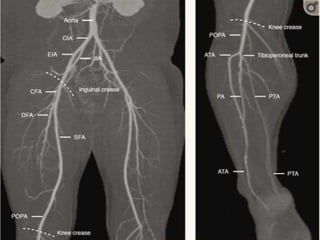

⦁ The arteries of the lower limb arise at the bifurcation of the

abdominal aorta (Fig. 4-1), the common iliac arteries run

down the posterior wall of the pelvis and divide into the

internal and external iliac arteries in front of the sacroiliac

joint.

⦁ The common femoral artery runs from the inguinal ligament

to its division into superficial and deep femoral arteries in the

upper thigh; this division is usually 3–6 cm distal to the

inguinal ligament.

⦁ The deep femoral artery, or profunda femoris artery, passes

posterolaterally to supply the major thigh muscles.

⦁ The importance of the profunda femoris lies in its role as a

major collateral pathway in patients with significant

superficial femoral artery disease.

⦁ The superficial femoral artery (also referred to as the femoral

artery) passes downwards along the anteromedial aspect of

the thigh lying anterior to the vein; in the lower third of the

thigh it passes into the adductor canal.

⦁ Passing posteriorly behind the lower femur it enters the

popliteal fossa and becomes the popliteal artery, which lies

anterior to the popliteal vein and gives off several branches,

the largest of which are the superior and inferior geniculate

arteries.

⦁ Below the knee joint the popliteal artery divides into the

anterior tibial artery and the tibioperoneal trunk, although

the exact level of the division may vary; after 2–4 cm the

latter divides into the posterior tibial artery and the peroneal

artery.